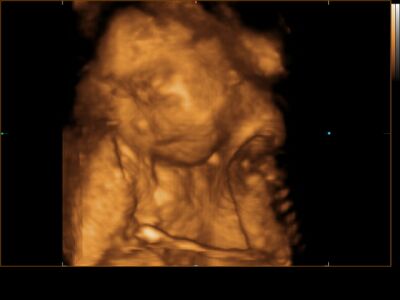

Az arcát a hátsó falba a placentába fúrta, így aztán kitűnő képek készültek a háterincéről meg néha a füléről

Na, azért van egy homályos fél arcocska is